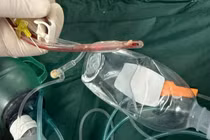

Sau hội chẩn chuyên khoa, các bác sĩ đã chỉ định nội soi phế quản cấp cứu để lấy dị vật. Thủ thuật được tiến hành an toàn, dị vật là đầu ngòi bút nhựa được lấy ra hoàn toàn sau hơn 30 phút và không ghi nhận biến chứng trong và sau can thiệp.

Dị vật là đầu ngòi bút, bề dày thành khoảng 1,8mm, chiều dài khoảng 18mm. (Nguồn: Bệnh viện Phụ sản-Nhi Đà Nẵng)